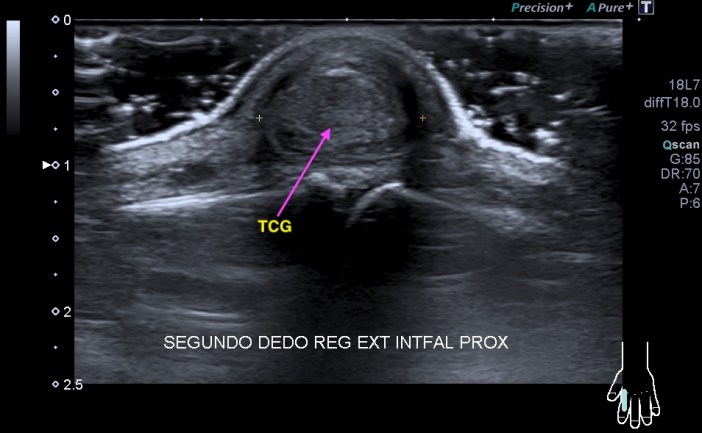

Tumores de Células gigantes:

• Se originan en la vaina tendinosa

• Localmente agresivos

• Afecta asiduamente a los tres primeros dedos de la mano y a los dos primeros de los pies.

• Mas hipoecogénica homogénea no depresible y bien definida.